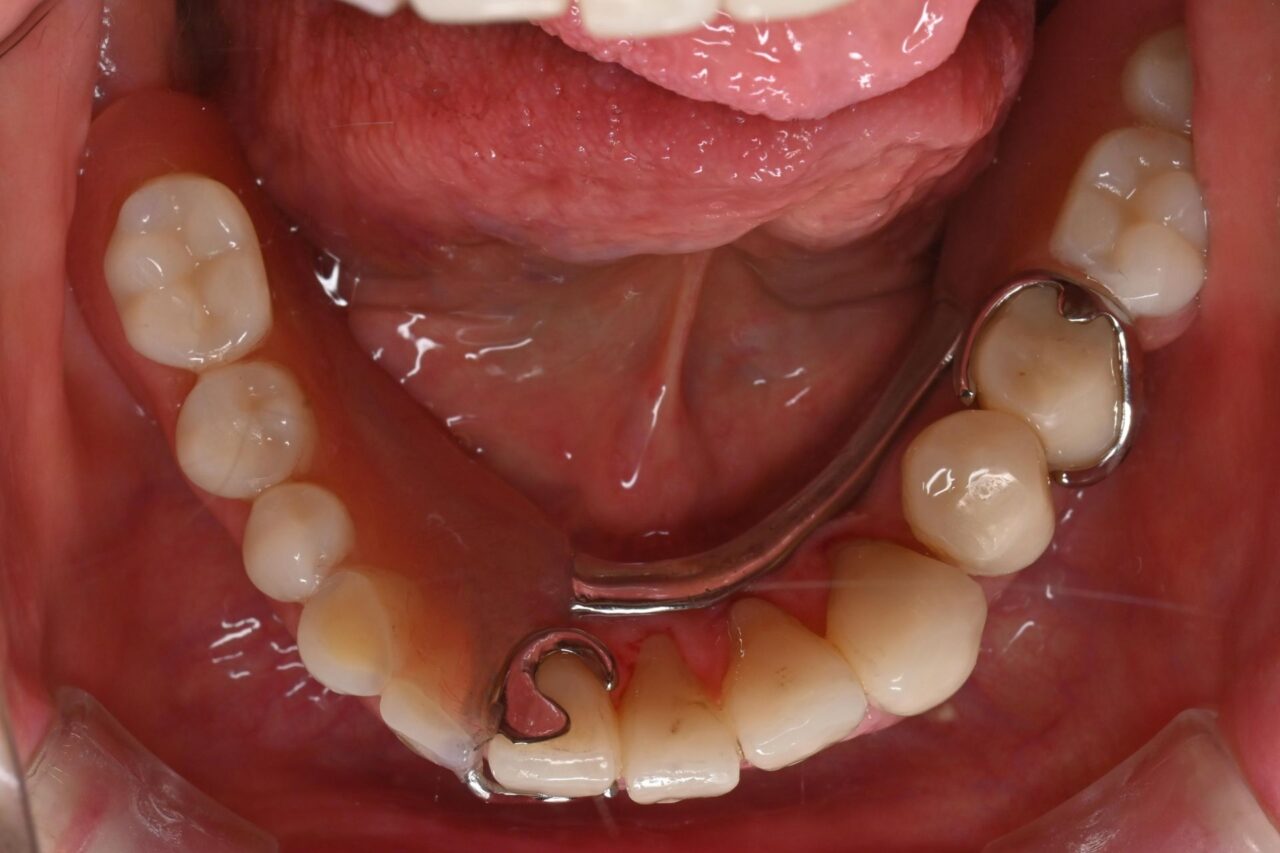

下面

親知らずが残っていますね。

びわ湖大津デンタルクリニックでは、不要な親知らずは即抜歯です。

ブリッジも不衛生かつ虫歯になっていますので、迷わず撤去。

入れ歯以外の自分の歯は全て保険のCAD/CAMに置き換えました。